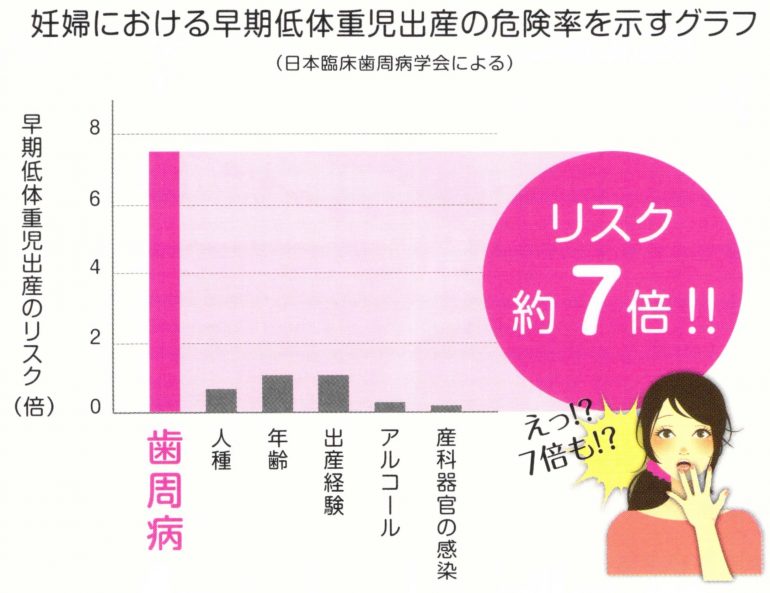

妊娠中や授乳中の方

歯周病菌の殺菌・抑制

歯周病菌は低体重児や早産のリスクを高めるため妊娠中は歯周病菌の殺菌が重要です。

また歯周病菌は夫婦間で唾液感染するため、新しい命を守るために夫婦で歯周病菌を殺菌しましょう。